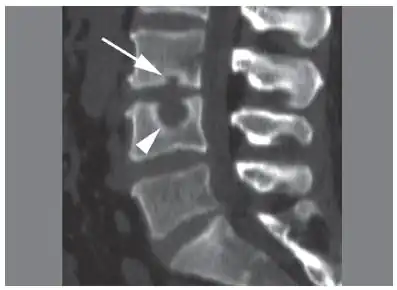

CT scan in the sagittal plane of two Schmorl's nodes. The small Schmorl's node at the inferior endplate of the L3 vertebral body (arrow) has typical features, being broad-based at the endplate, with well-defined contours and thin marginal sclerosis. A large and less typical Schmorl's node (arrowhead) is observed at the superior endplate of L4.[3]